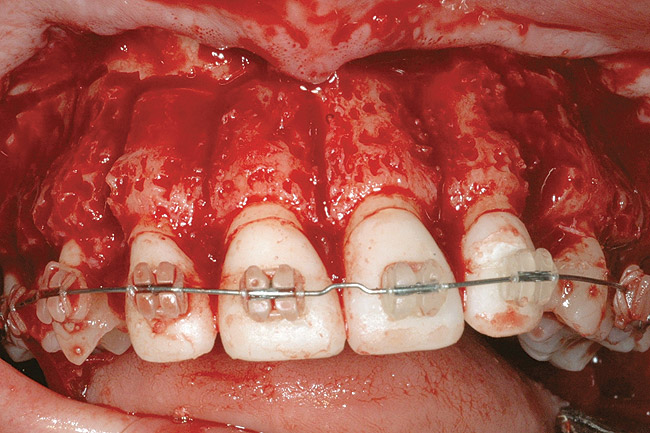

Fig 4. Note gingival inflammation caused by biologic width violation. Provisional restorations were placed on Nos. 6, 8, 9, and 11, and corticotomies were performed from Nos. 3 to 14.

Figure 4

Fig 5. One week postsurgery with mesial buildups on Nos. 5 and 12 and thin pontics on archwire to conceal spaces during closure.

Figure 5

Fig 10. A corticotomy in SFOT is a surgical technique in which only the cortical bone is cut, perforated, or mechanically altered to the depth of the medullary bone and the medullary bone remains intact.

Figure 10